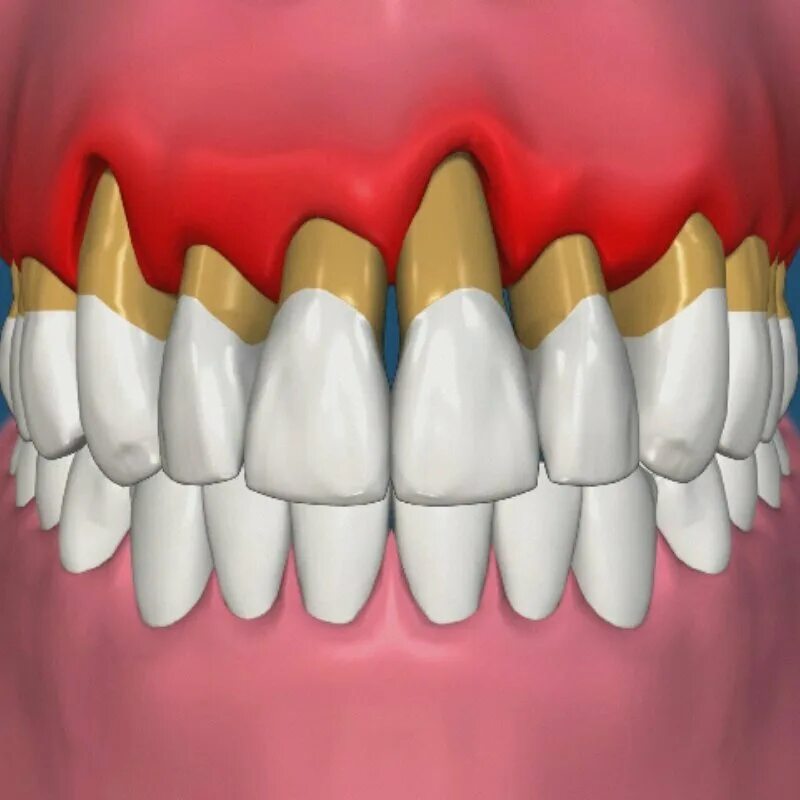

Зубной карман